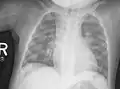

Au niveau du thorax, le chapelet costal clinique donne un aspect radiologique, surtout visible de profil, « en bouchon de champagne » des jonctions chondro-osseuses. En sus des déformations osseuses, on peut observer des atteintes pulmonaires par troubles de la ventilation.

Radiographie du thorax.